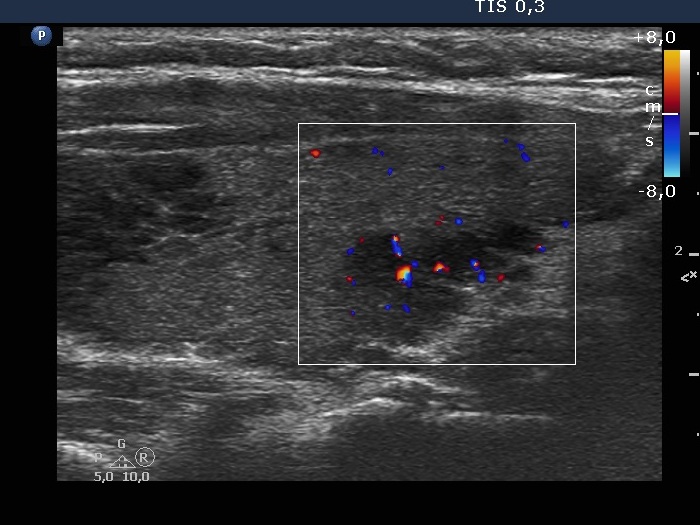

Ultrasonography. The thyroid was minimally hypoechogenic and had several discrete more hypoechogenic areas, including a cluster composed of multiple discrete lesions in the dorsal part of the left lobe. These lesions had irregular, partly lobulated, partly spiculated margins. However, the entire pattern corresponded to Hashimoto's thyroiditis.

Regarding the nodule borders the lesions presented partly lobulated, partly spiculated margins. However, these should not be held as pathological nodules, the discrete lesions are presentations of more active foci of Hashimoto's thyroiditis, which is an infiltrative process and therefore frequently has infiltrative, irregular margins.